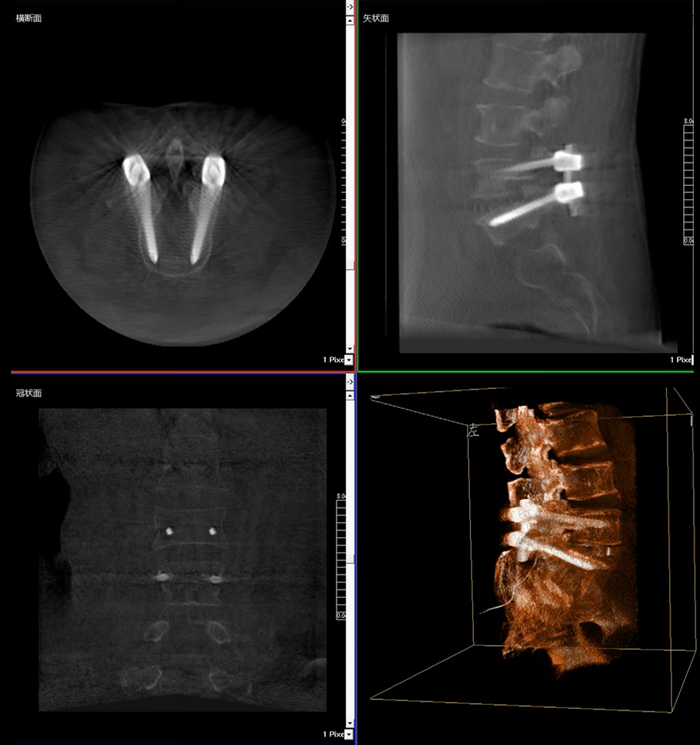

移动式三维C形臂,又称骨科三维C臂,就是将传统二维与“类CT模式”相结合的升级版C形臂,能在术中快速地生成横断面、矢状面、冠状面断层图像和三维立体图像。通过不同方位的断层图像,能够更清晰、完整地显示椎体及其附件的解剖学结果,直观地分析病变与周围组织的立体空间关系,三维断层成像能够使手术模拟和手术方案的制定更加准确。

而三维影像的MPR图像组可以通过不同平面的切分,使成像区内更丰富的信息得以呈现。尤其是二维影像无法涉及的横断面,提供了另一个空间维度的信息量。

在MPR图像中,冠状面、矢状面和横断面的信息大大提高了医生对于病灶区以及手术效果的判定。